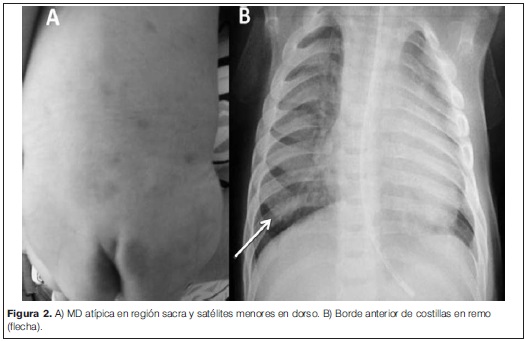

Lactante de 3 meses, sexo masculino, producto de una primera gestación sin complicaciones. Padres sanos, no consanguíneos. Sin patología del parto ni perinatal, datos antropométricos normales al nacer. Como antecedentes se destacan laringomalacia congénita, tres infecciones respiratorias que requirieron internación por insuficiencia respiratoria, retraso en el desarrollo motor, trastorno deglutorio y hernia inguinal derecha operada. Al examen se constata reactivo, sonrisa social, fija y sigue con la mirada, fascies tosca con retrognatia, narinas antevertidas, raíz nasal ancha y deprimida, sinofris, hepatomegalia, hipotonía global de predominio axial, no parética, con reflejos osteotendinosos vivos, clonus de pie izquierdo. A nivel de piel se evidencia extensa melanosis dérmica en dorso y múltiples satélites más pequeñas (figura 2A). La evaluación oftalmológica evidenció opacidades corneanas bilaterales. De la paraclínica se destaca: tomografía computada de cráneo, perfil tiroideo, gasometría venosa, función renal y hepática, creatina quinasa en sangre, amoniemia, lactacidemia y hemograma normales. La serología para citomegalovirus, rubeola y toxoplasmosis resultaron negativas. Los potenciales evocados visuales y auditivos mostraron una disfunción bilateral. La radiografía de tórax mostró un ensanchamiento del sector anterior de las costillas (costillas en remo) (figura 2B). Se objetivó un aumento de los mucopolisacáridos en orina. La deficiencia en la actividad enzimática de la a-L-iduronidasa en sangre, con valores de 0,6 mmol/l/h (normal mayor a 2,5 mmol/l/h), confirmó el diagnóstico de MPS tipo I.